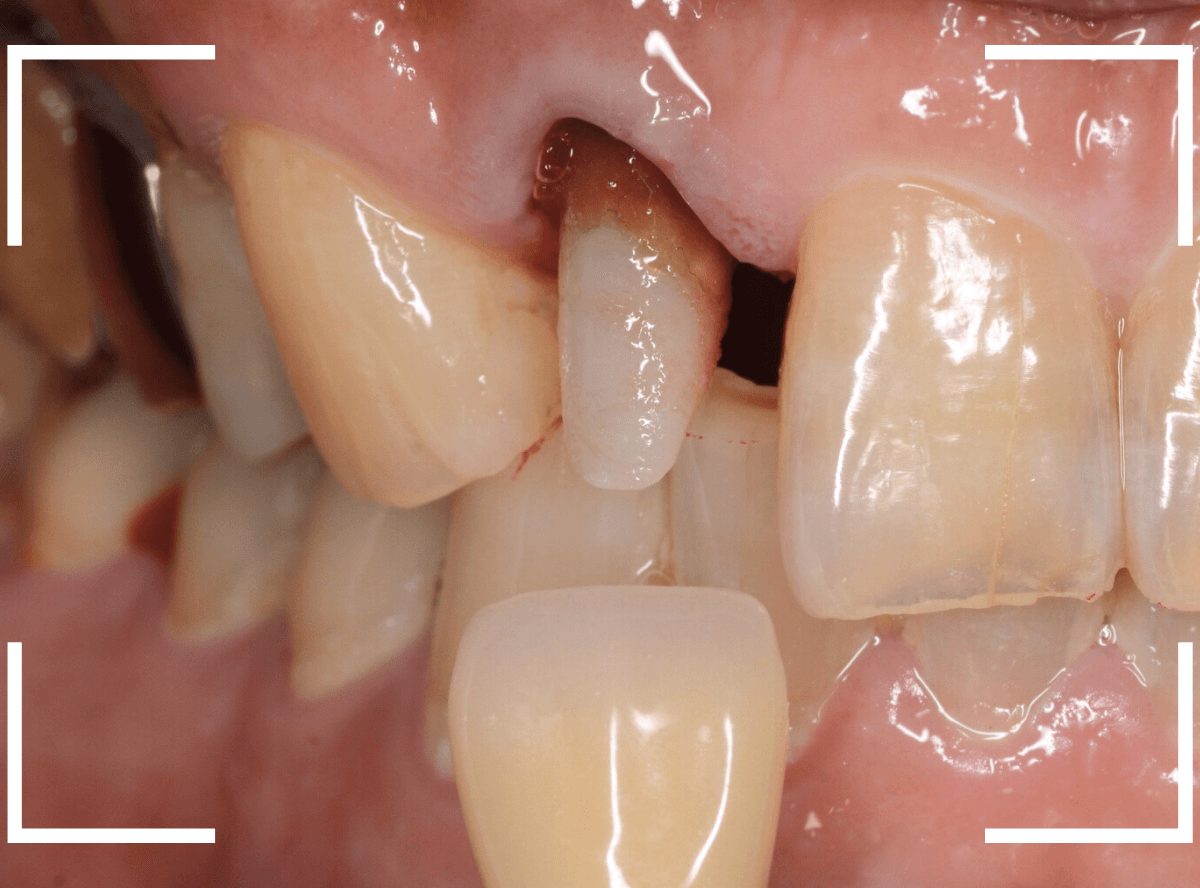

お口の中でsetしたところです。

お口の中に入った状態のビフォーアフターです。

見た目の印象も大きく変わったかと思います。

また、以前のさし歯に比べて、舌触りがとてもよくなったとの感想もいただきました。

恥ずかしながら、私自身もセラミックのさし歯をいれていますが、同じ感想でした。

舌触りが滑らか=汚れがたまりづらく、虫歯や歯周病になりづらい、という健康上のメリットも大きいです。